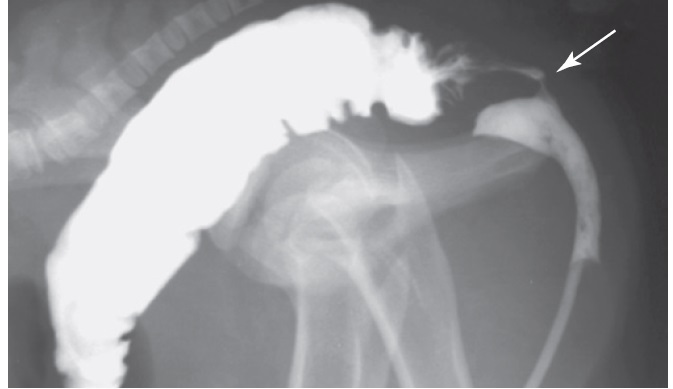

A positive contrast urethrogram in a 3-day-old burro thatpresented with atresia ani and intermittent passage of fecal material fromthe urethra. A catheter was passed via the urethra and contrast agentwas injected, resulting in accumulation of a large amount of contrastagent in the rectum and a lesser amount in the intrapelvic portion of theurethra. A small amount of contrast agent can be seen in the urethrorectalfistula (arrow).